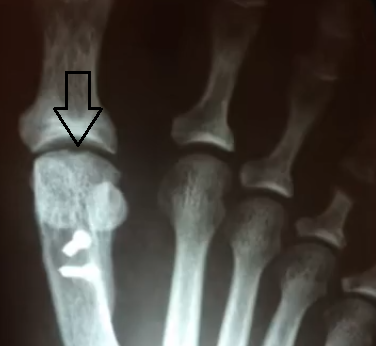

• Quais as principais alterações na radiografia?

A

• Depressão no domo da cabeça do 1° metatarso (artrose inicial)

• Artrose na art. mtfl

• Osteófito dorsal na cabeça do 1° mtt

• Na avaliação radiográfica, qual o 1° sinal a aparecer?